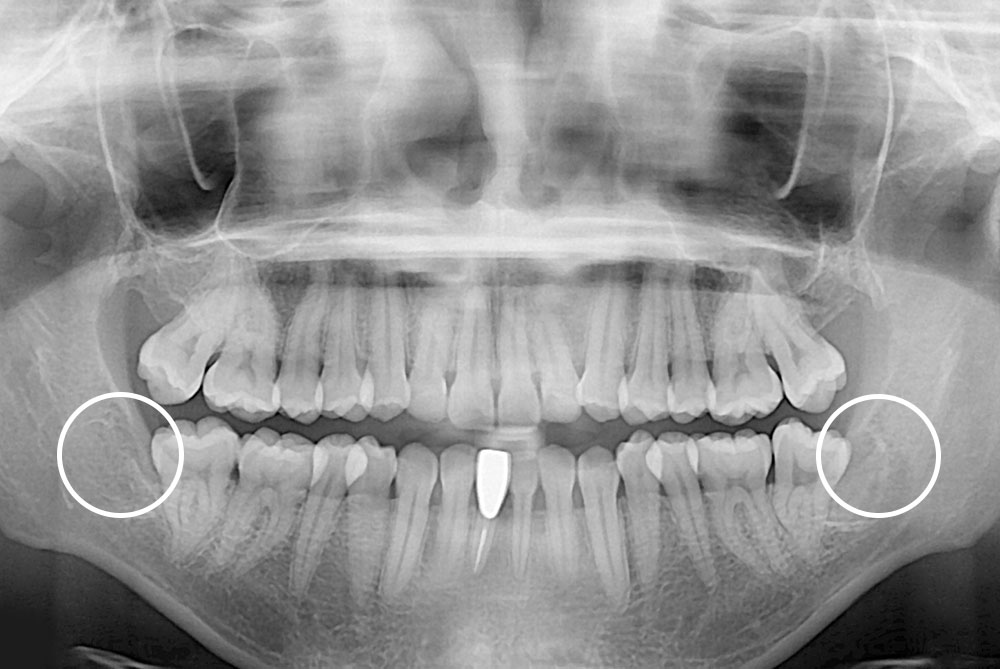

[사랑니] 매복 사랑니 발치

치료후 : 2020-03-09

세종치과는 구강악안면외과학 박사이신 원장님이 발치하는 치과입니다.